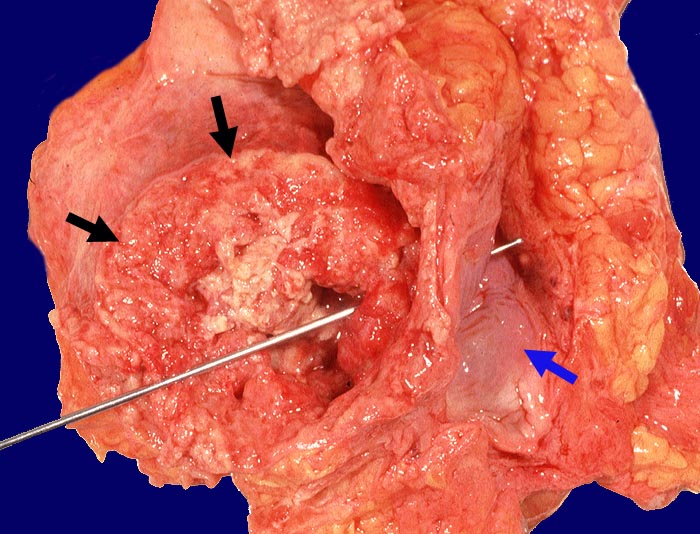

Bei den invasiven Urothelkarzinomen der Harnblase unterscheidet man nach dem Wachstumsmuster papilläre und solide Karzinome. Invasive Urothelkarzinome weisen oft deutlichen Zellatypien auf (geringer Differenzierungsgrad). Zumindest herdförmige plattenepitheliale oder adenomatöse Differenzierungen (Metaplasien) kommen oft vor und haben keine prognostische Bedeutung. Eine Ausnahme bilden kleinzellige Karzinomanteile, die die Prognose deutlich verschlechtern. Ausserhalb des invasiven Karzinoms zeigt das Urothel gehäuft ein Carcinoma in situ. (> 3629) (> 3401).

Wenn keine Metastasen vorliegen, kann ein Patient durch radikale operative Eingriffe (Zystektomie mit pelviner Lymphknotendissektion, Nephrektomie) geheilt werden. Bei inoperablen Patienten sollten eine potentiell kurative Bestrahlung oder Chemo-/Radiotherapie erhalten. Bei den primär metastasierten Urothelkarzinomen versprechen Chemotherapien einen guten palliativen Effekt.

Makroskopie

Befund

Pathologischer Befund